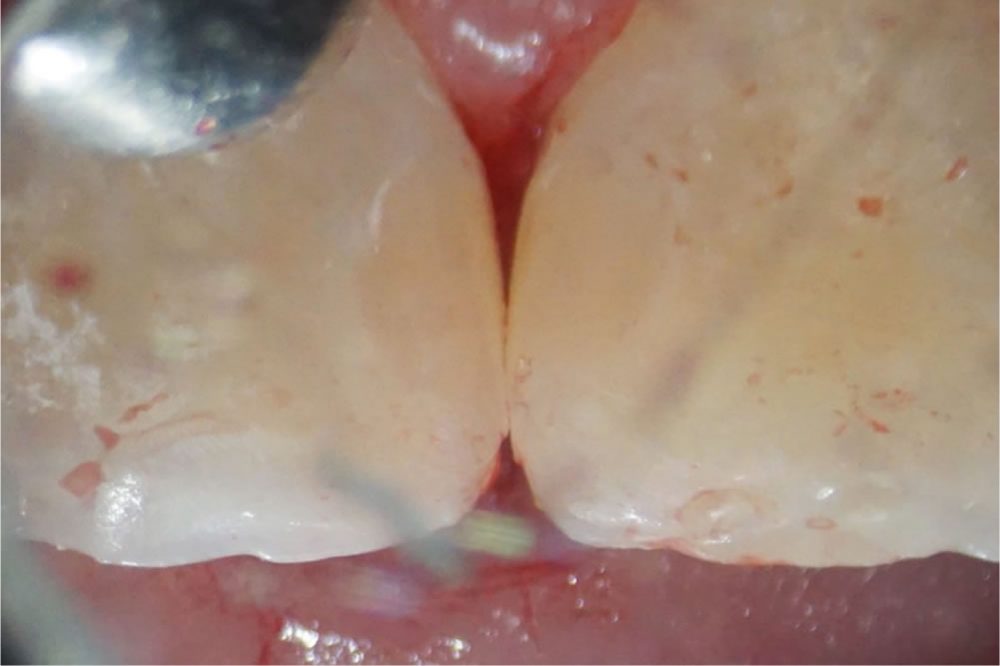

行徳スマイル歯科で実施したCR治療の症例をご紹介

正面(写真左)から見ると、何も異常がないように見えますが、上顎前歯の裏側(隣り合った歯と歯の接触している部分)が虫歯になっていました。

虫歯除去後にCRを充填して治療完了

象牙質まで達していた虫歯(C2/中度虫歯)を、丁寧に取り除いた後にCRを充填して治療完了です。CR(コンポジットレジン)による虫歯治療は、一度の治療で完治していますが、なるべく長持ちさせるために患者様ご自身で、術後の管理(今回の場合は歯ブラシ+フロスの使用など)と定期的な歯科医院でのチェックが必須になります。